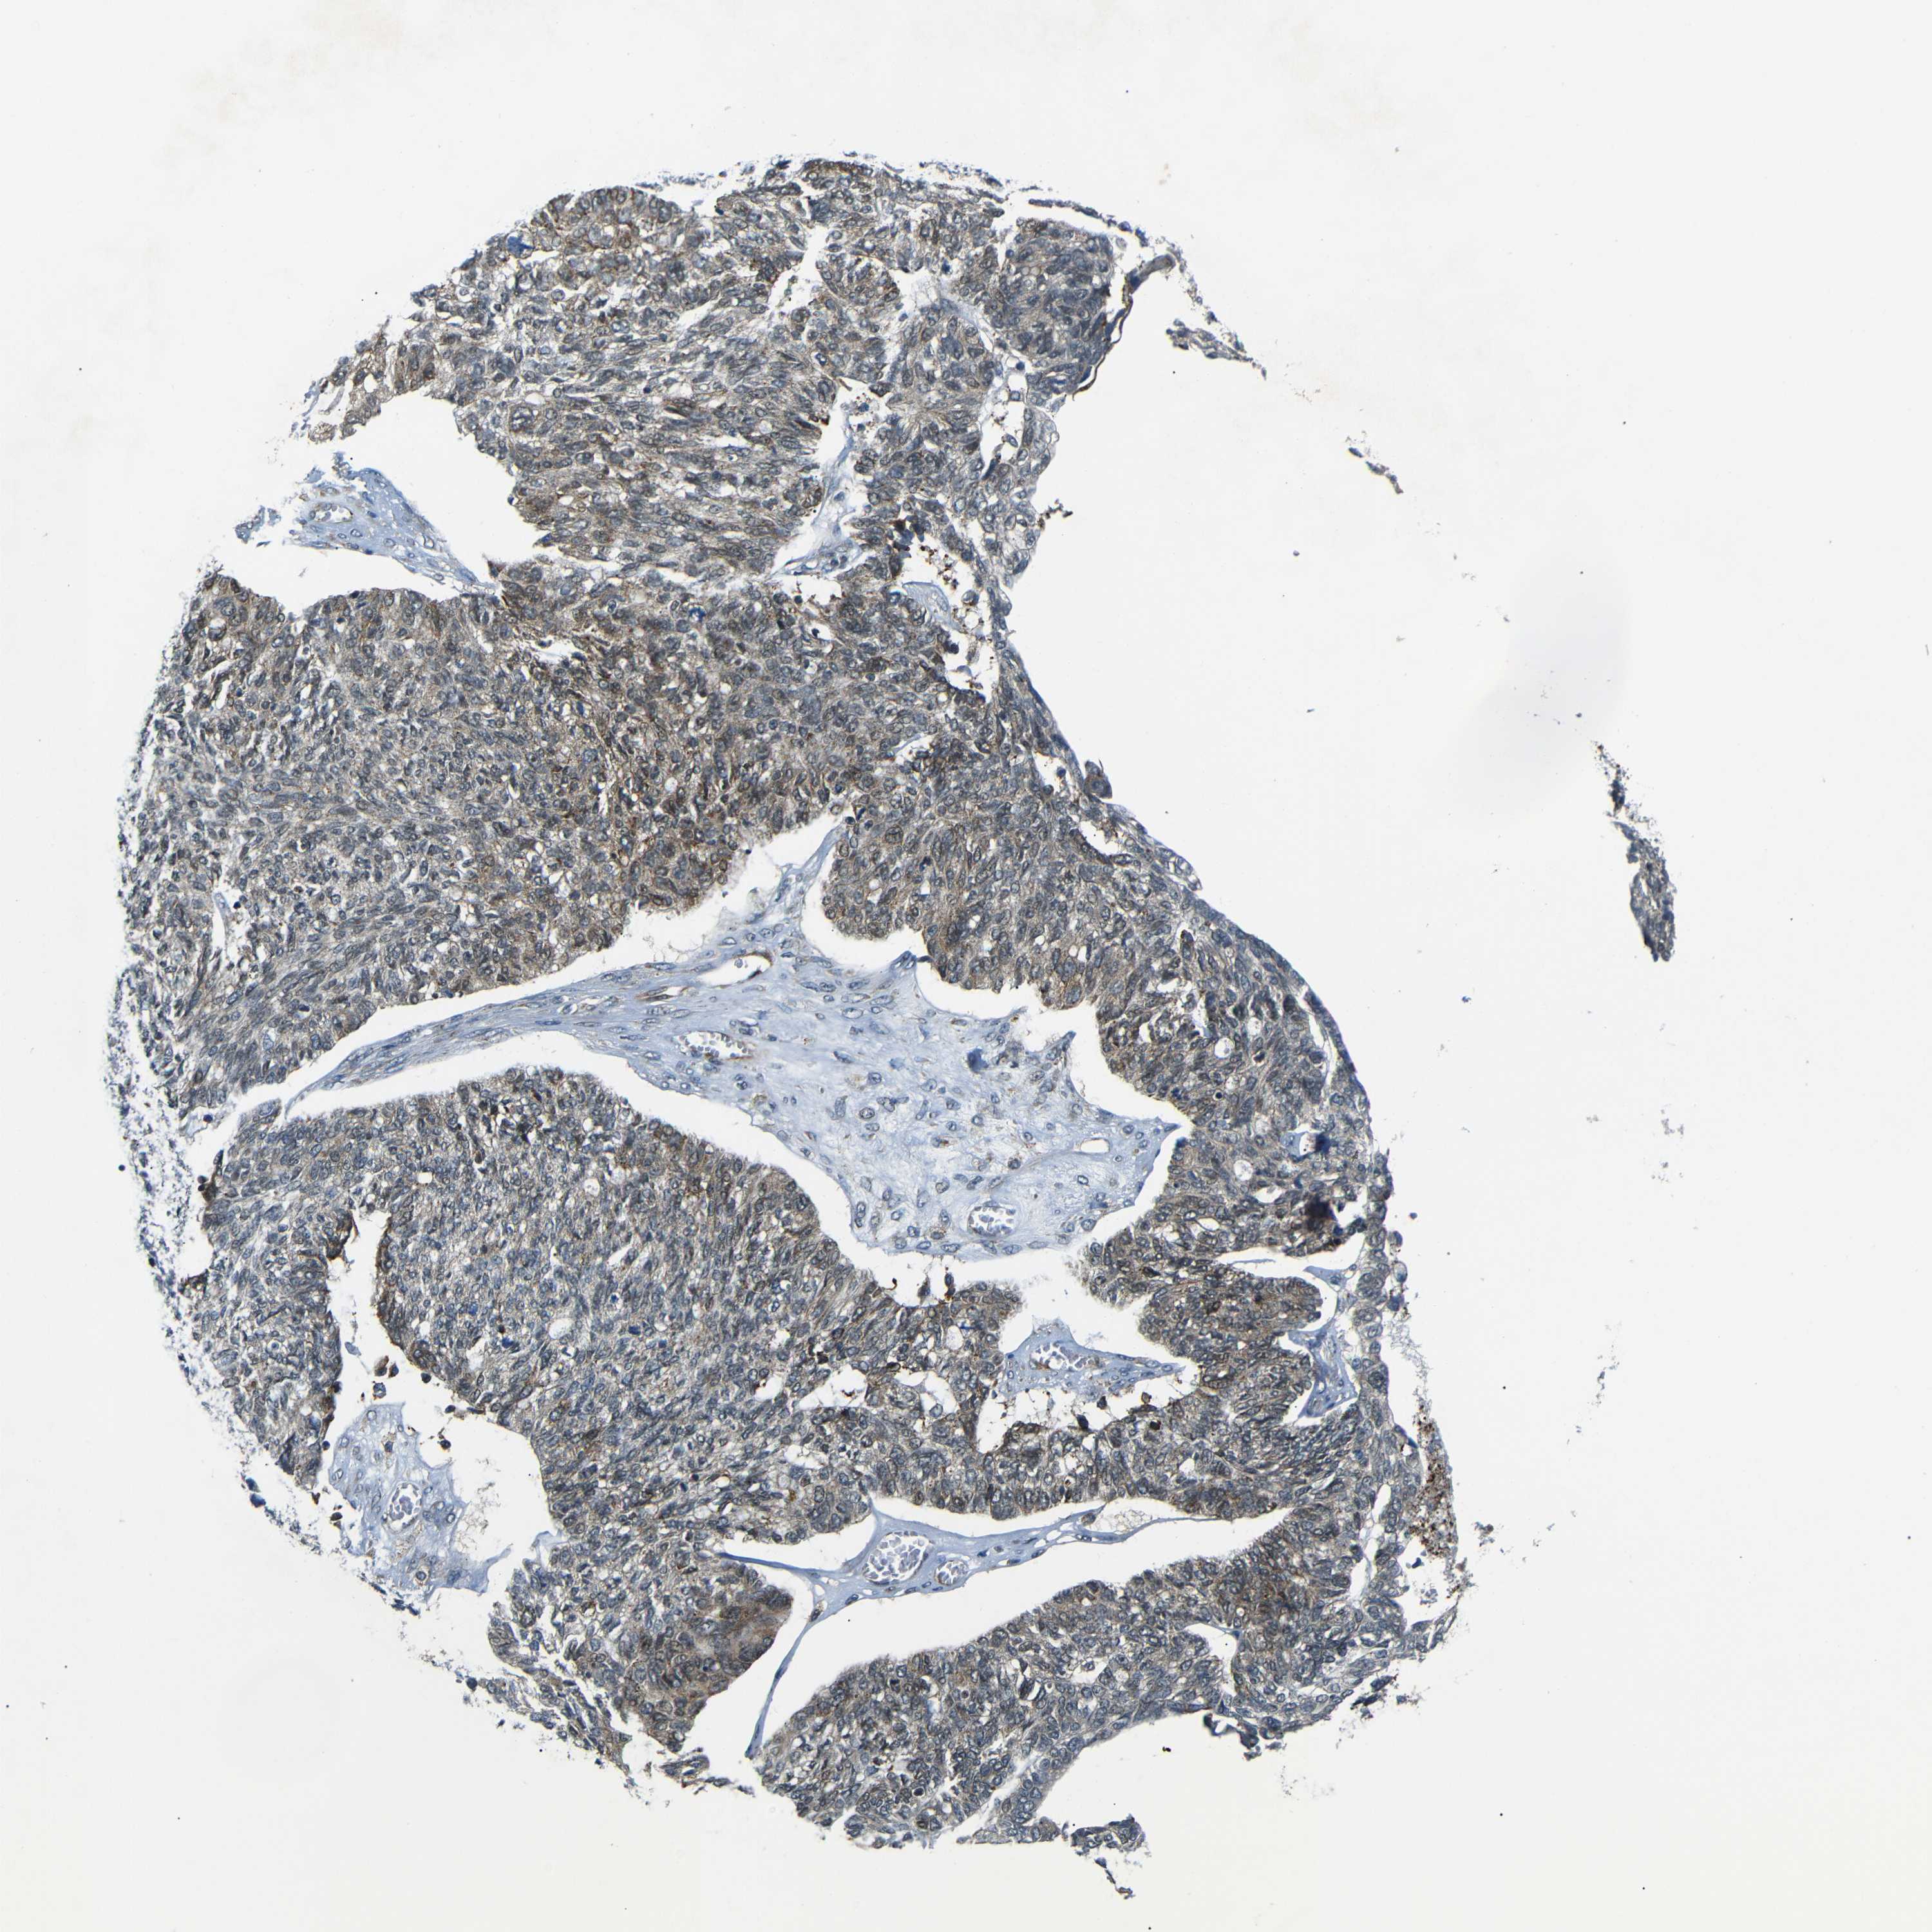

OVARIAN CANCER - Protein expressioni

A mouse-over function shows sample information and annotation data. Click on an image to view it in a full screen mode. Samples can be filtered based on level of antibody staining by selecting one or several of the following categories: high, medium, low and not detected. The assay and annotation is described here.

Note that samples used for immunohistochemistry by the Human Protein Atlas do not correspond to samples in the TCGA dataset.

Antibody stainingi

Antibody staining in the annotated cell types in the current human tissue is reported as not detected, low, medium, or high, based on conventional immunohistochemistry profiling in selected tissues. This score is based on the combination of the staining intensity and fraction of stained cells.

Each image is clickable and will lead to virtual microscopy that enables deeper exploration of all samples and also displays staining intensity scores, fraction scores and subcellular localization as well as patient and tissue information for each sample.

Antibody HPA013328

Cystadenocarcinoma, serous, NOS

Carcinoma, endometroid

Cystadenocarcinoma, mucinous, NOS

Carcinoma, NOS